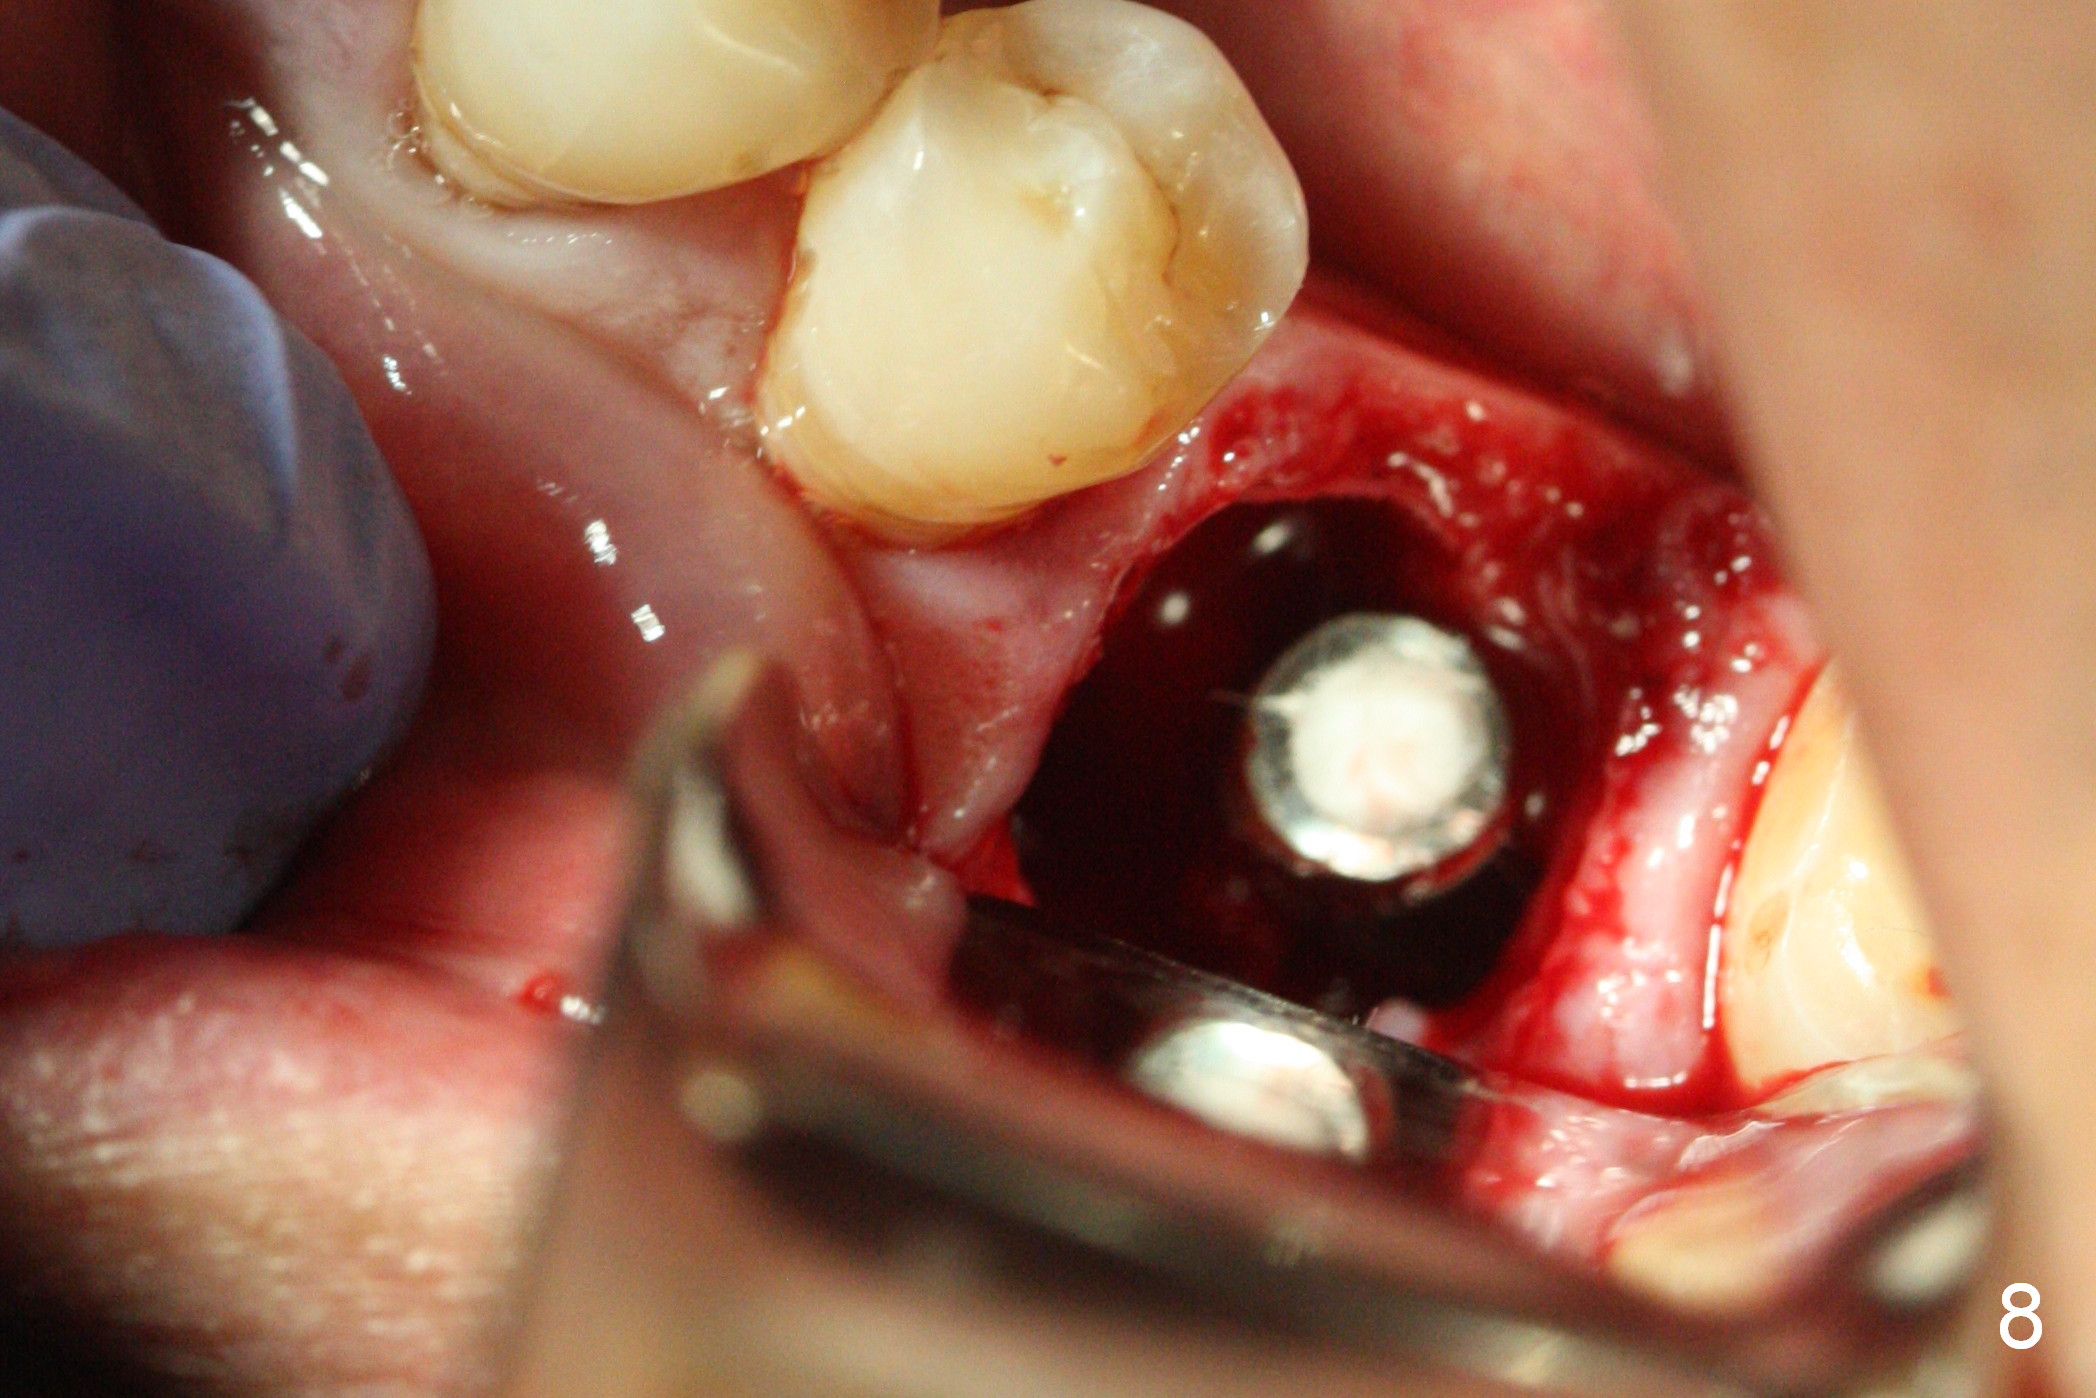

The asymptomatic tooth (#19) has a midbuccal fistula (Fig.1 <). The mesiobuccal pocket is 10 mm with purulent discharge from the sulcus (Fig.2,3). The mesiobuccal wall defect is confirmed when the tooth is extracted. Osteotomy is initiated lingually in the septum following septal crestoplasty (flattening) (Fig.4: using 1.6 mm drill for 9 mm). Since the lingual portion of the osteotomy is higher, it is difficult to use drill with stopper. For the narrow septum osteotomy, multiple drills are used sequentially (Fig.5 after 4.3 mm drill). A 4.5x11 mm dummy implant is placed (Fig.6) apparently too deep. When a 5x11 mm IBS implant is being placed, the depth is tightly controlled (Fig.7). The implant is apical to the lingual crest, whereas there is ~ 2 mm implant exposure buccally. That is, there is a large gap mesiobuccally (Fig.8), which is filled with .5-1.5 mm allograft (Fig.9 *). A 6.5x5.7(3) mm abutment (A) is placed and trimmed for an immediate provisional (Fig.10 P). The lacerated buccal gingiva is sutured as well as application of Perio Glue.